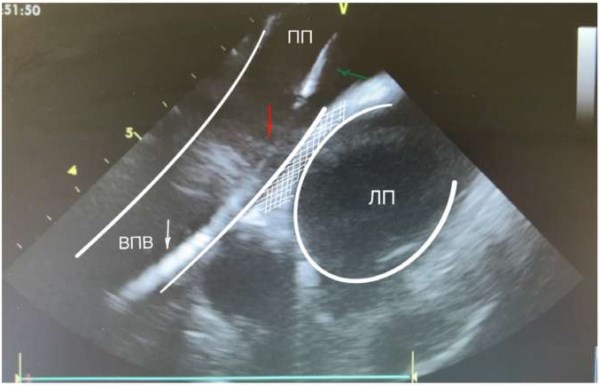

После проведения датчика в правое предсердие (ПП) его ось ориентируется на 12 ч (нос пациента в положении на спине без поворота головы), что отражается УЗ «домашней позицией», ориентиры ПП, трикуспидальный клапан, правый желудочек, корень аорты (рис. 2). Для безопасного позиционирования проводника транссептального интродьюсера необходимо визуализировать ВПВ. Следующее движение УЗ датчика — поворот по часовой стрелке на 3 ч. Анатомические ориентиры: ПП, левое предсердие (ЛП), межпредсердная перегородка, корень аорты, из этой позиции визуализируется ушко ЛП (рис. 3), при отсутствии признаков тромбоза принимается окончательное решение о проведении процедуры в ЛП. Для выведения ВПВ с помощью верхнего и нижнего колец управления луч датчика поворачивается кзади и вправо на 45°. Анатомические ориентиры: ВПВ, восходящая аорта, ЛП. Проводник через НПВ, ПП заводится в ВПВ под УЗ контролем и далее по нему транссептальный интродьюсер (рис. 4). После замены проводника на транссептальную иглу управляющие кольца УЗ датчика возвращаются в нейтральную позицию для визуализации межпредсердной перегородки, интродьюсер с иглой смещается вниз на овальную ямку. При затруднении пункции телом иглы возможна пункция внутренним стилетом с дальнейшим поэтапным проведением иглы на стилет, дилататора на иглу, интродьюсера на дилататор (рис. 5). По проведенному через интродьюсер в левую верхнюю ЛВ жёсткому проводнику проводится смена интродьюсера на доставляющее устройство для криобаллона. Выведенный за пределы доставляющего устройства баллон и циркулярный катетер хорошо определяются визуально (рис. 5), также показателем выведения баллона является метка на катетере. Управляя УЗ катетером вращением по и против часовой стрелки, а также с помощью управляющих колец изгибая катетер вперёд-назад и вправо-влево выводятся поочерёдно (по часовой стрелке) левые ЛВ, далее правая нижняя и правая верхняя ЛВ (рис. 6, 7). Стимуляционный катетер проводится в правый желудочек из «домашней позиции», а ВПВ по описанной ранее методике. Контроль окклюзии УЛВ осуществляется с помощью цветной допплероскопии (рис. 8, 9) и «пузырьковой пробы», для чего в просвет криобаллонного катетера вводится физиологический раствор. Контроль полости перикарда проводится из ПП (поворот из «домашней позиции» против часовой стрелки) и из правого желудочка (загибание управляющим кольцом кпереди), эту манипуляцию мы проводим как во время процедуры, так и перед завершением и извлечением УЗ катетера.

Рис. 4. На изображении выведены: проводник (белая стрелка) с шифтом (зеленая стрелка) и бужом (красная стрелка) в ВПВ. Белым контуром выделены ВПВ и ЛП. Стенка ВПВ, переходящая на межпредсердную перегородку (заштрихованная белым зона).

Сокращения: ВПВ — верхняя полая вена, ЛП — левое предсердие, ПП — правое предсердие.